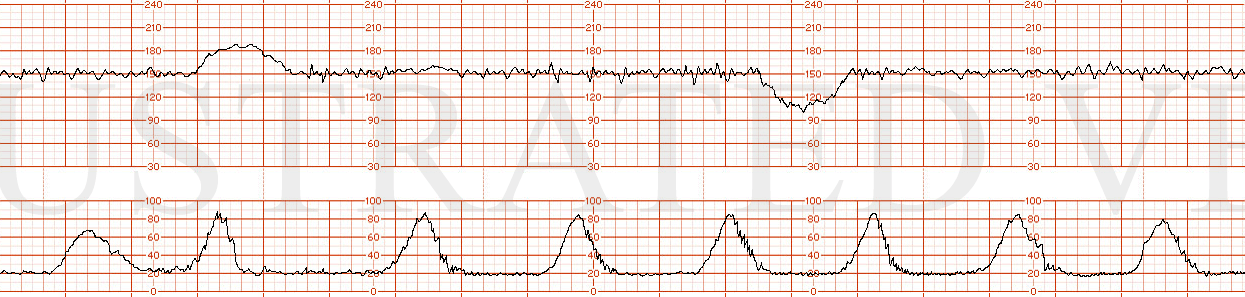

3. At 2300 hours, Ms. X was dilated to 7 cm, 90% effaced, and at -1 station. At 2315 hrs, the fetal heart rate tracing showed minimal variability, no accelerations, and excessive uterine activity. At this time, the EFM strip was Category 2.

4. On March 4, 20XX, after midnight, the fetal tracing still showed minimal variability, no accelerations, excessive uterine activity, and new prolonged decelerations. At 0017, Ms. X ruptured membranes. The fluid was determined to be clear. Ms. X was noted to be 9.5 cm, 100% effaced, and at 0 station. At 0030, Dr. Doe was advised by telephone of the decelerations on the fetal monitor.

5. The fetal monitor tracing continued to show prolonged decelerations that were worsening and severe variable decelerations to 60 starting at 0043 hrs. At 0120, Ms. X was 10cm dilated/100% effaced, and 0 station. The EFM tracing continued to show minimal variability, prolonged decelerations, and excessive uterine activity. At 0143, the doctor was notified by phone that Ms. X was complete.

*Please note: EFM strips presented here are random stock images illustrating Category II and one Category III EFM tracing. They are not true representations of monitor tracings from the actual case. mmh